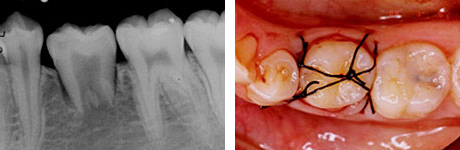

根管治療直後。歯根が完成している歯を移植歯として用いた場合、歯の神経はつながらないので、このように神経の治療が必要になります。

移植後4ヶ月。

移植歯はコンポジットレジンで修復が行われています。